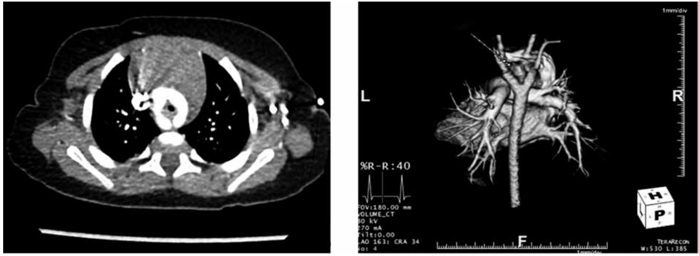

Mãe de lactente de um ano refere que seu filho apresenta chiado no peito desce o nascimento. Vem sendo tratado como bronquiolite desde então. Procurou novo pediatra que o encaminhou ao cardiopediatra. Mãe apesar de desconfiada passou em consulta e realizou radiografia de tórax normal, eletrocardiograma normal, ecocardiograma que viu alguma alteração na aorta nada conclusivo e angiotomografia e tomografia de tórax.

Com base nessas ilustrações, qual seu diagnóstico?